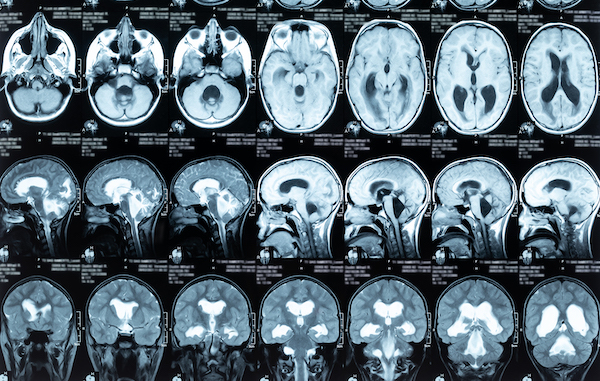

Brain

Aging; Brain

Back and Spine; Brain; Rehabilitation

Brain; COVID; Heart

Brain; Discovery